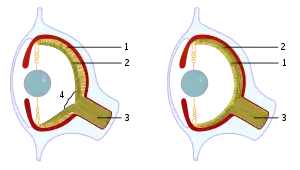

A blind spot, scotoma, is an obscuration of the visual field. A particular blind spot known as the physiological blind spot, "blind point", or punctum caecum in medical literature, is the place in the visual field that corresponds to the lack of light-detecting photoreceptor cells on the optic disc of the retina where the optic nerve passes through the optic disc.[2] Because there are no cells to detect light on the optic disc, the corresponding part of the field of vision is invisible. Processes in the brain interpolate the blind spot based on surrounding detail and information from the other eye, so it is not normally perceived.

Although all vertebrates have this blind spot, cephalopod eyes, which are only superficially similar because they evolved independently, do not. In them, the optic nerve approaches the receptors from behind, so it does not create a break in the retina.

The blind spot in humans is located about 12–15° temporally and 1.5° below the horizontal and is roughly 7.5° high and 5.5° wide.[3]